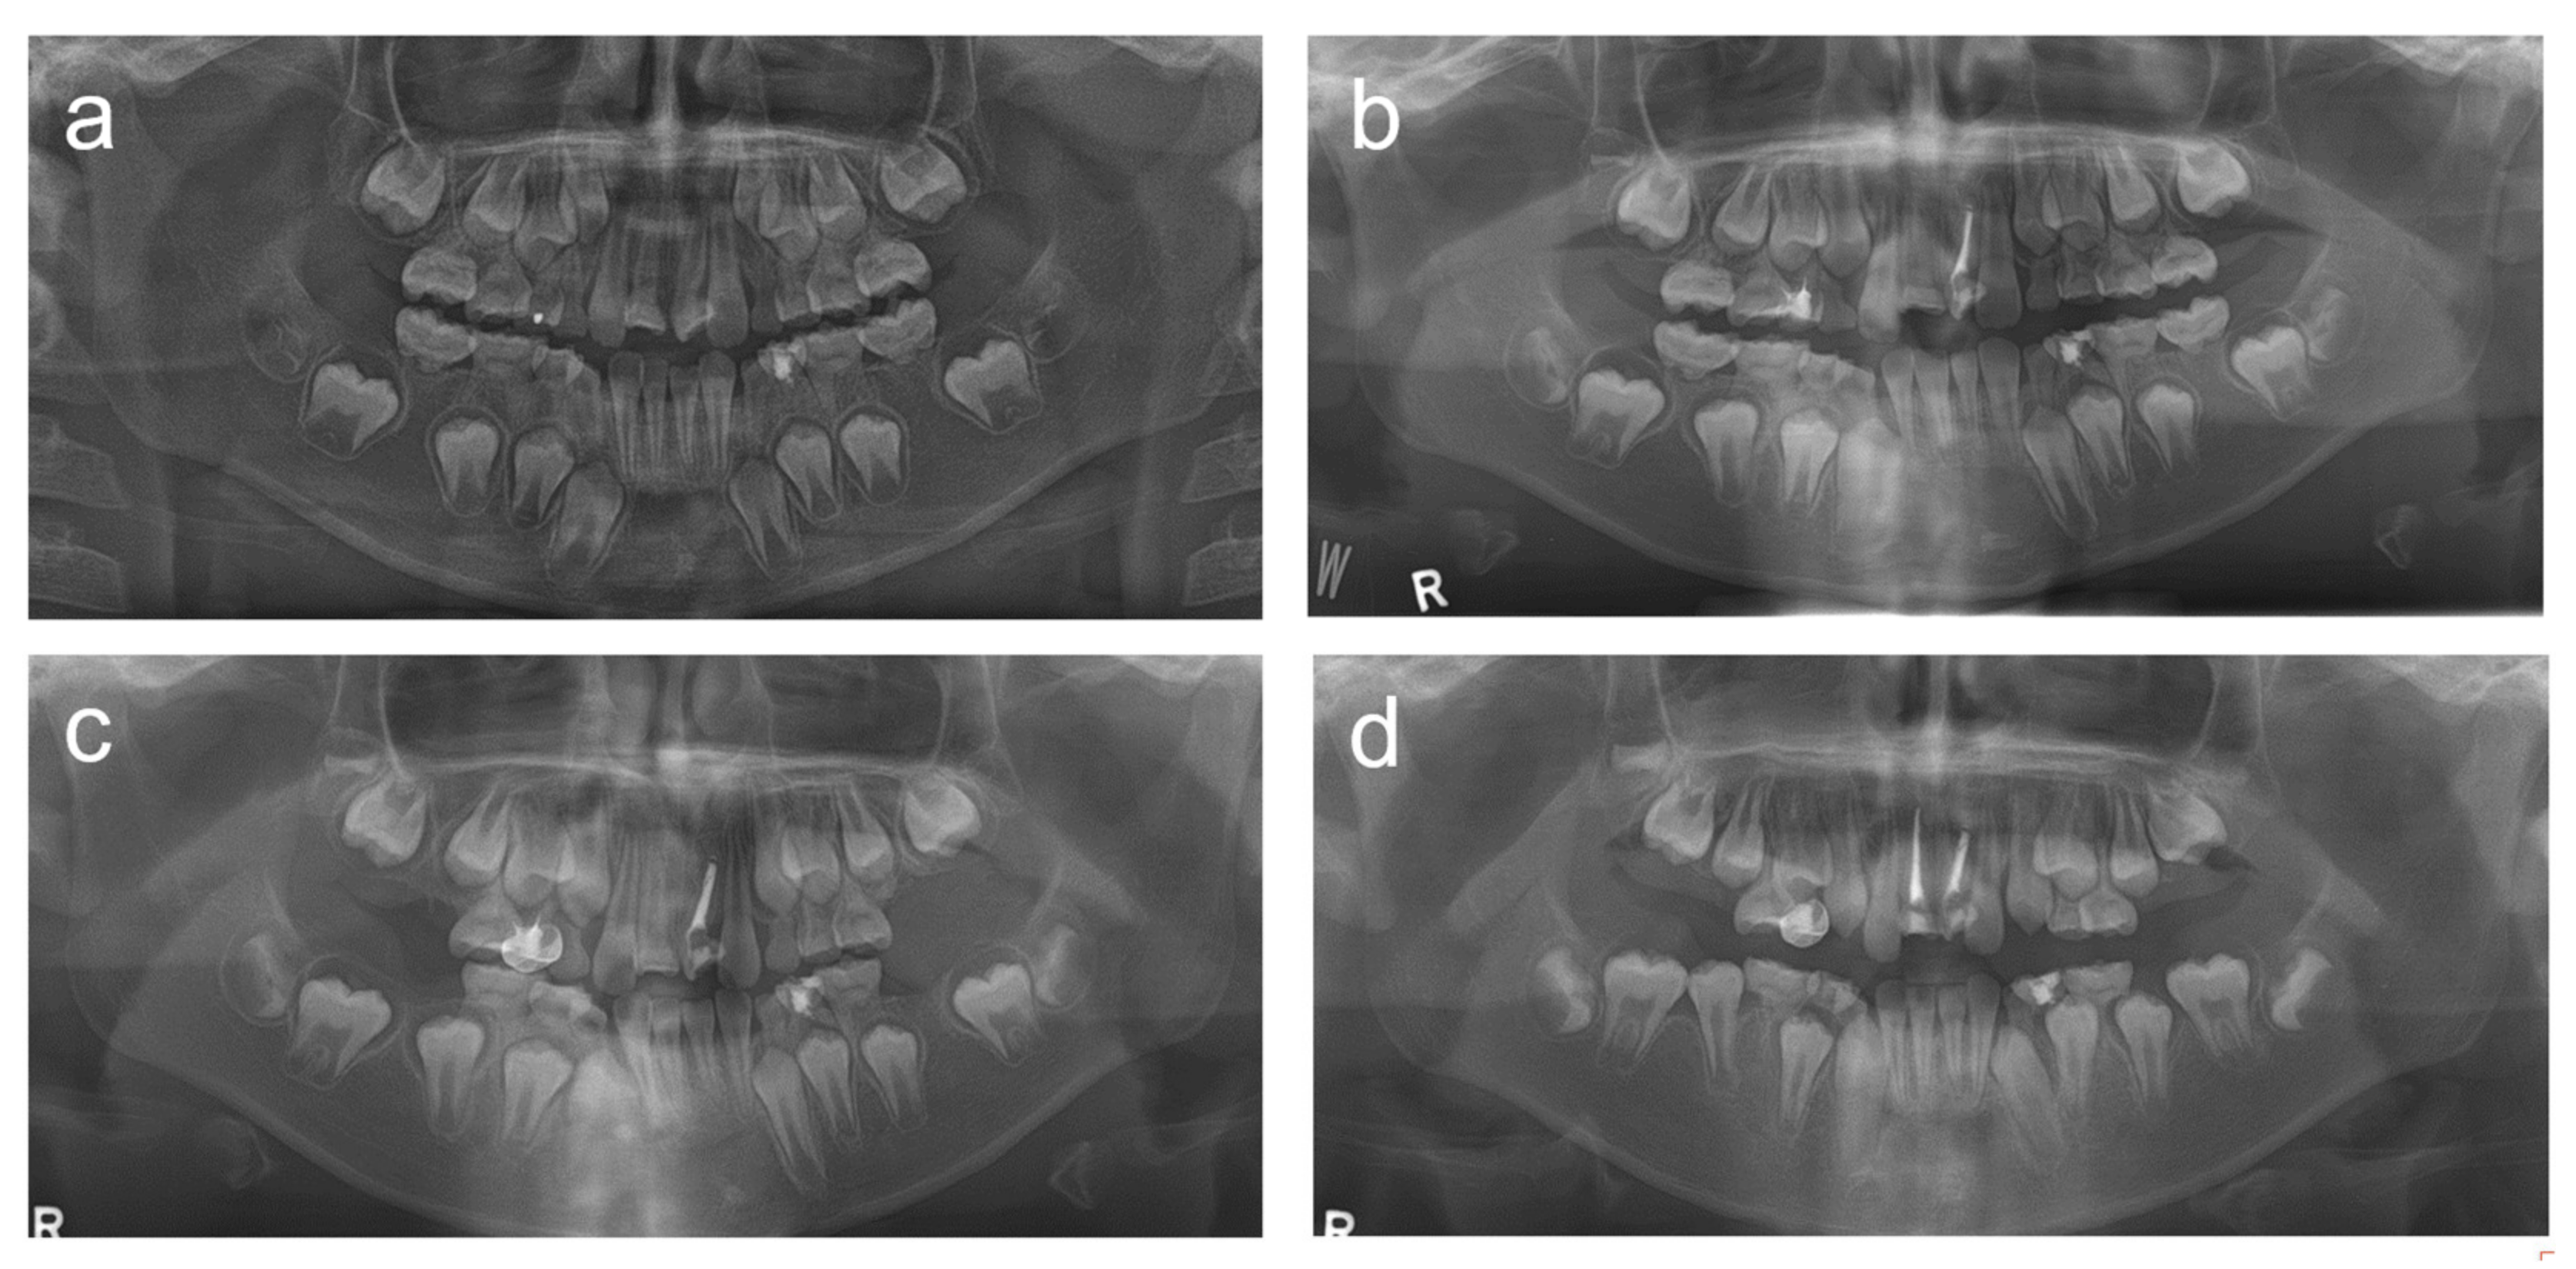

2.1. Case 1

2.2. Case 2

2.3. Case 3

2.4. Case 4